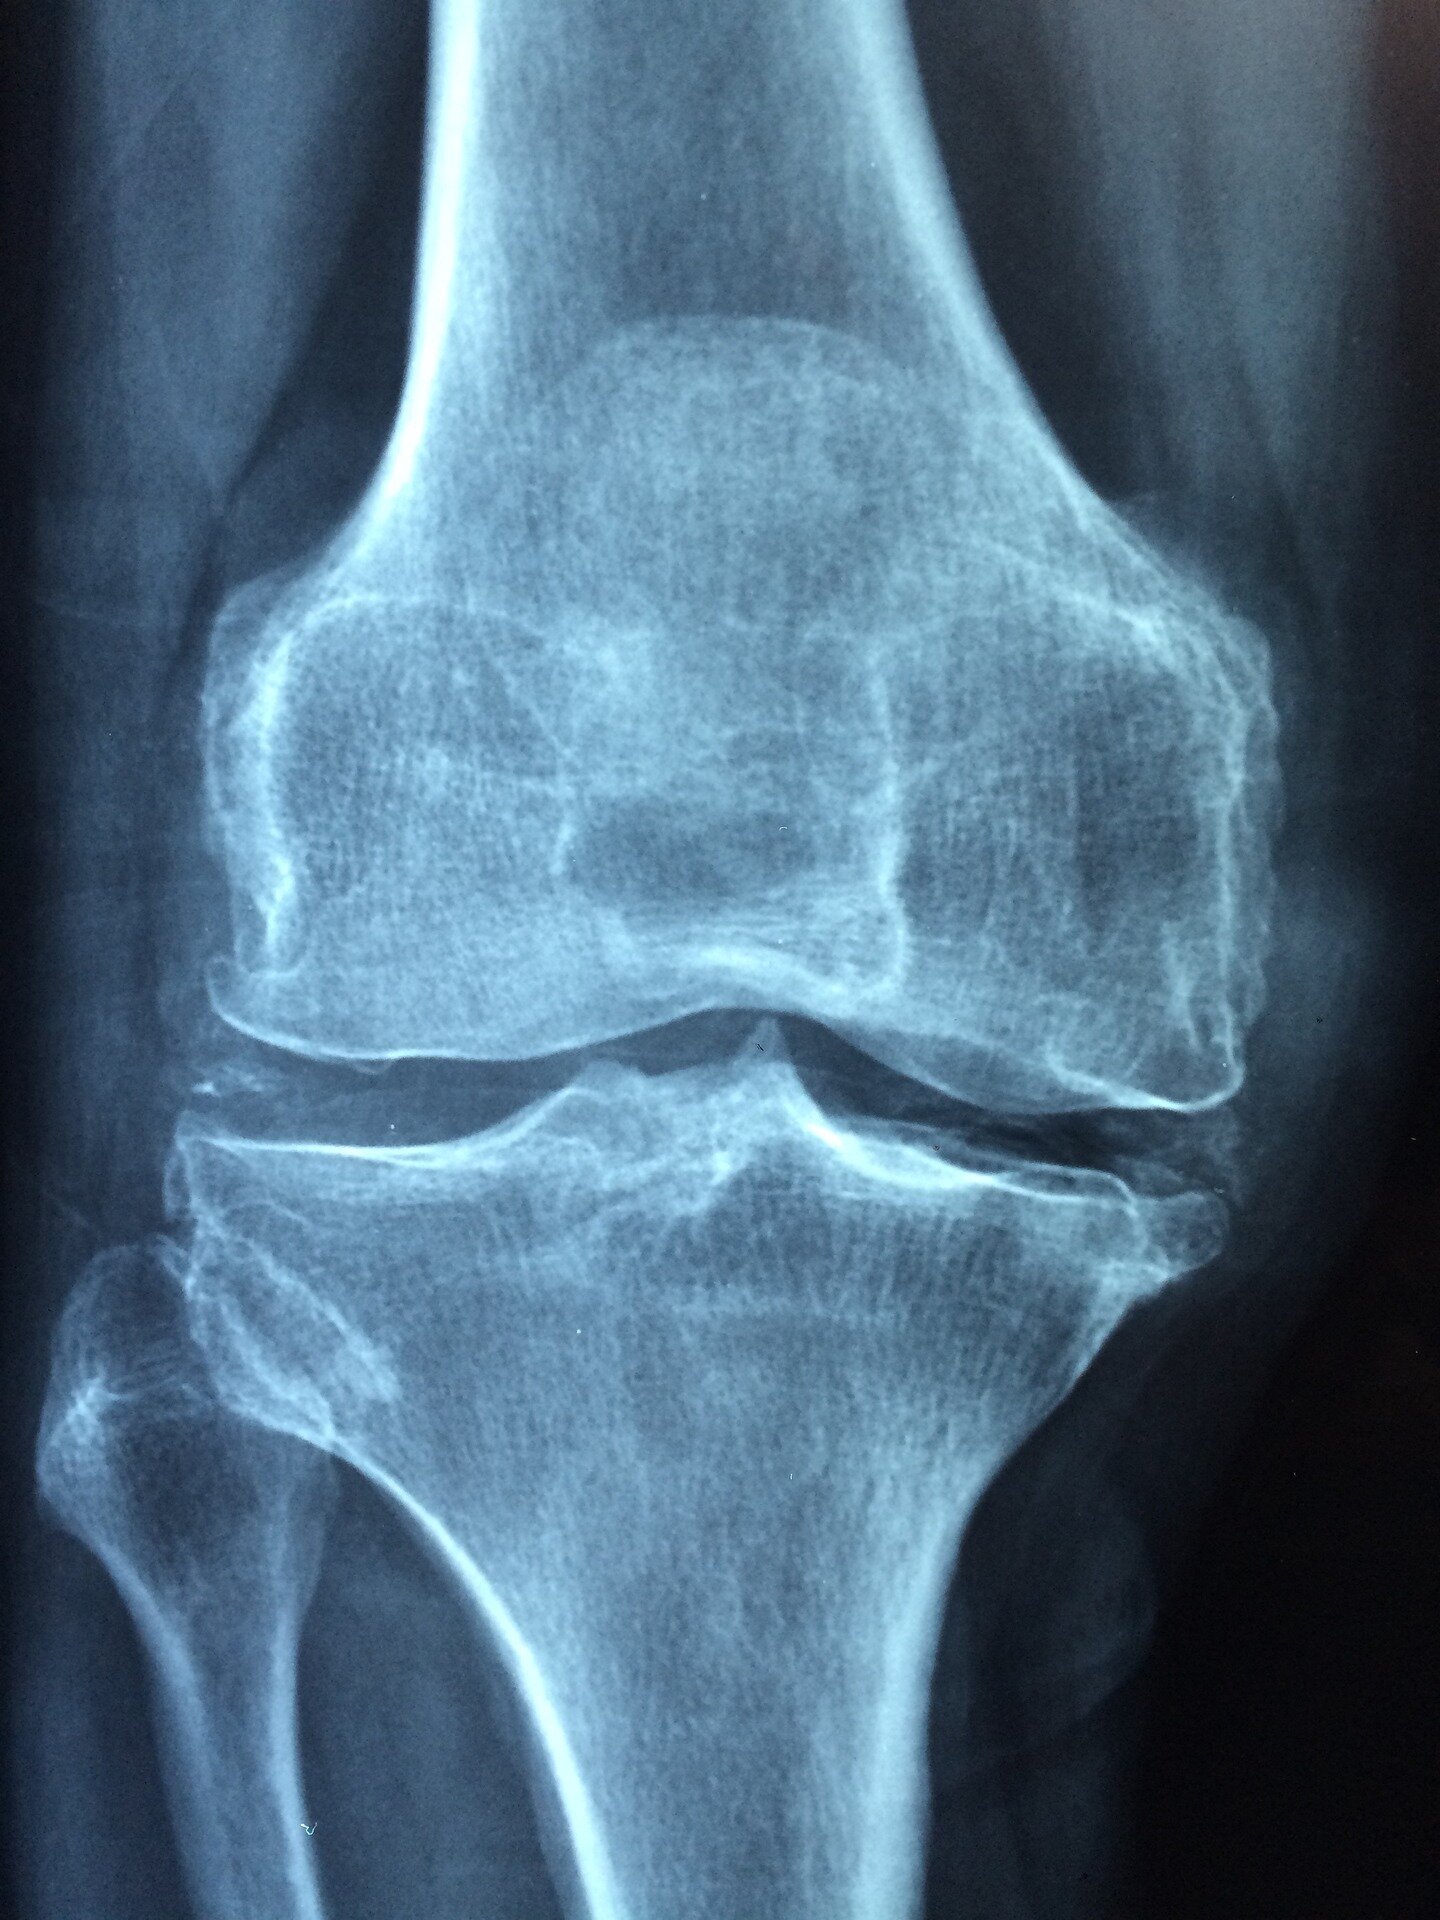

Bien que l’augmentation de l’espérance de vie moyenne témoigne de la médecine moderne et des efforts de santé publique, une population vieillissante s’accompagne d’une présence accrue de maladies chroniques telles que l’ostéoporose.

• De 2005 à 2018, il y a eu une augmentation significative du nombre global d’individus qui souffrent d’ostéoporose aux États-Unis

• L’ostéoporose a augmenté dans tous les groupes d’âge, à l’exception de ces 80 ans et plus.

• Il a été démontré que les femmes blanches non hispaniques ont la prévalence la plus élevée d’ostéoporose diagnostiquée.

• Près de 70% des personnes atteintes d’ostéoporose n’ont pas été diagnostiquées, principalement des hommes, des Américains d’origine mexicaine et des individus âgés de 50 à 59 ans.

Cette étude est la première à évaluer les tendances d’ostéoporose non diagnostiquées au fil du temps, par l’ethnicité / race, le groupe d’âge et le sexe et l’ethnicité / race. Les résultats indiquent qu’il existe un plus grand besoin de soins proactifs pour la santé des os.